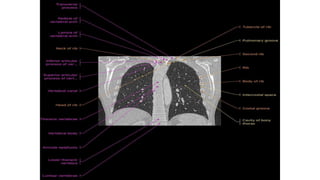

Thoracic spine

X-ray in AP and Lateral

projections.

Vertebral body (star ) of

T12 with rib hypoplasia;

T10–T11 intervertebral

foramina (circle ); T11

right pedicle(arrowhead )

Thoracic spine X-ray inAP and Lateral projections. Vertebral body (star ) of T12 with rib hypoplasia; T10–T11 intervertebral foramina (circle ); T11 right pedicle(arrowhead )